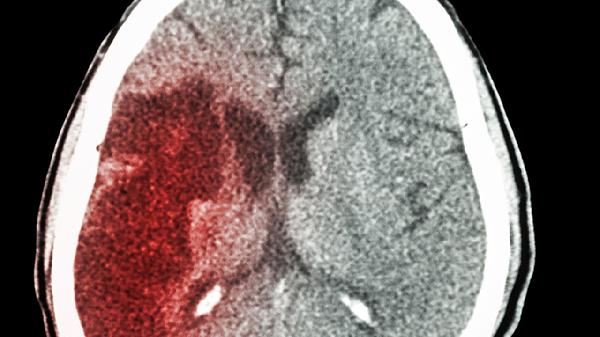

五、管理好慢性病

1、控制血压血糖